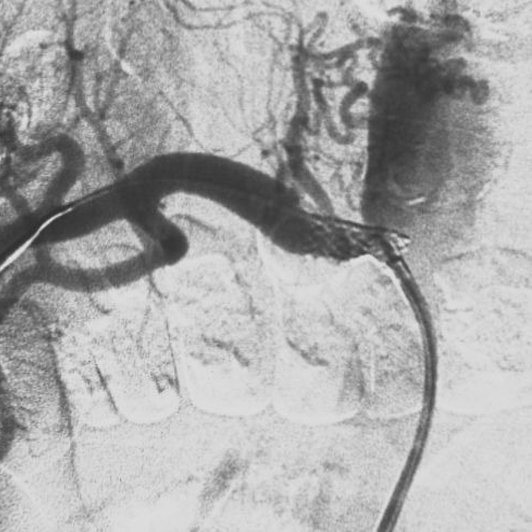

Outcomes observed in patients treated with image-guided, minimally invasive vascular procedures.

Results vary by patient and condition. Images are for educational purposes only.